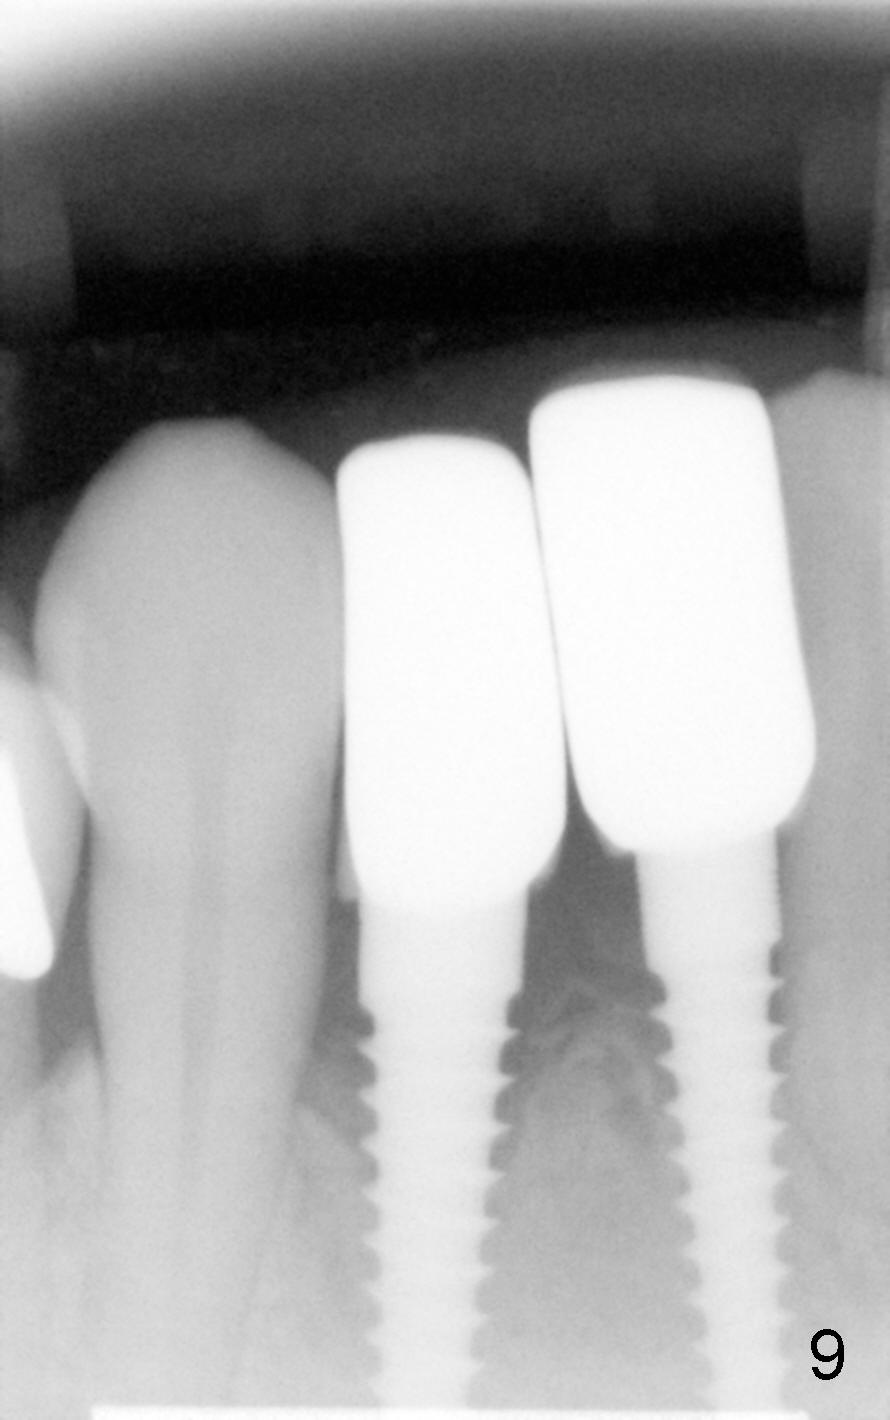

A 60-year-old lady wants to remove 2 mobile lower right incisors (Fig.1,2; with infection at the lateral (>)). Immediate 1-piece implants are placed (Fig.3,4): 3x17 mm at the central, 3.5x17 mm at the lateral. Insertion torque is > 60 Ncm for the implants. No bone graft is placed. After prep (Fig.5), two separate provisionals are fabricated (Fig.6). The one at the lateral incisor looks bulky at the cervix, because of the oversized implant for the site (over-engineering). Use of smaller implant (3.0 (instead of 3.5), 2.5 (instead of 3.0) or 2.0 mm) may solve the problem. Seven days postop, the infection resolves (Fig.7 >) with normal-looking papilla (*).

Fig.8,9,10 are taken 4 months postop, immediately and 2 years 2 months post cementation, respectively. They show that peri-implant gaps are reducing. There is no buccal atrophy atrophy 2 years 2 month post cementation (Fig.11 *).